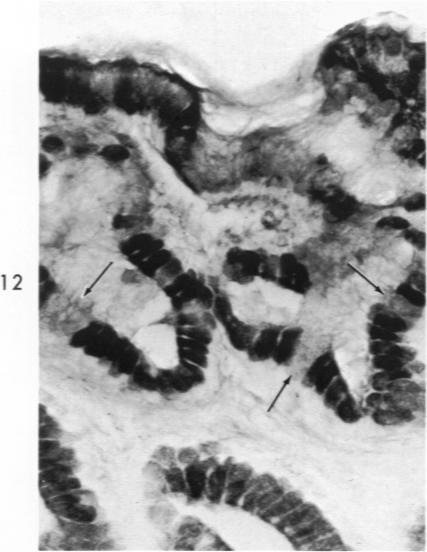

Histochemical and morphologic changes in gastric mucosa of dogs on ulcerogenic regimen.

Am J Pathol. 1969 Jul;56(1):129-51.